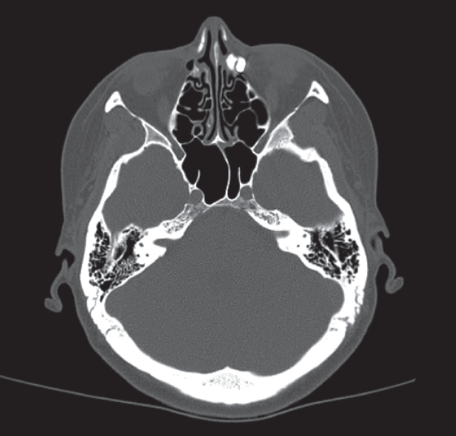

A series of images with multispiral computed tomography of the lacrimal passages demonstrated that the contrast agent completely filled the lacrimal sac, but did not enter the nasal cavity (Fig. 1). We decided to perform endoscopic endonasal dacryocystorhinostomy using a semiconductor diode laser in contact mode (2017). In the postoperative period, there were no complaints of lacrimation, while a free flow of liquid passed into the nose while rinsing. One year after the endoscopic surgery, the patient noted lacrimation again with periodic suppuration on the left. Relapse of chronic purulent dacryocystitis on the left was diagnosed. Considering the two previous surgical interventions for chronic purulent dacryocystitis of traumatic etiology and the history of an injury to the facial skeleton of the skull, we decided to perform a revision surgery with the placement of a bicanalicular silicone stent under the control of the surgery stages, with the use of navigation equipment.

Fig. 1. Multispiral computer tomography of nasal cavity, paranasal sinuses with contrast-enhancement of lacrimal pathways

Рис. 1. Мультиспиральная компьютерная томография полости носа, околоносовых пазух с контрастированием слёзных путей